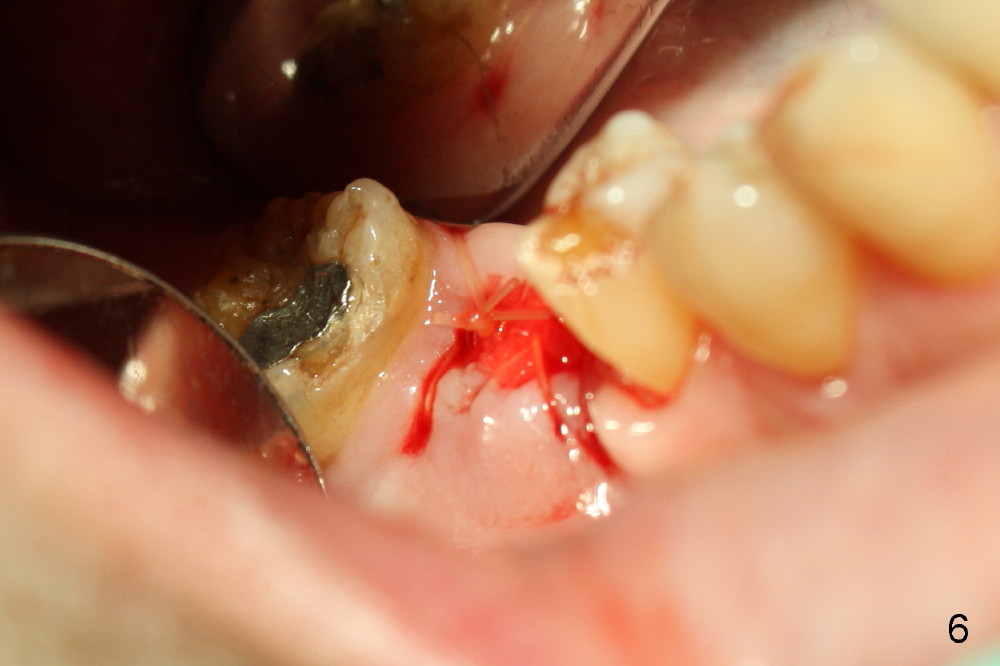

The tooth #30 was extracted in other office 1 month ago. The socket appears to heal normally. A tissue-level implant is placed as planned and smoothly. No antibiotic is prescribed pre- or post-op. The patient reports mild pain 1 week postop. There is a sign of infection. Amoxicillin is prescribed. One week later, the symptom improves, but the infection signs are present (Fig.1). The implant has mobility and is removed (Fig.2). The osteotomy is thoroughly debrided, followed by copious irrigation with normal saline and Clindamycin soaking. Irradiated cancellous bone graft (.5 mg) is placed (Fig.3,4). The wound is covered by collagen plug (Fig.5) and sutured with Chromic gut (Fig.6). Amoxicilin is prescribed postop. One week follow up reveals normal wound healing (Fig.7 (buccal view), 8 (lingual)).